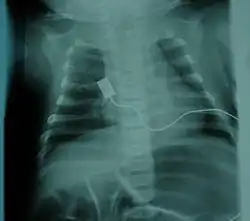

RTG klatki piersiowej dziecka z SWS, widać wąską klatkę piersiową, ale prawidłowe granice serca